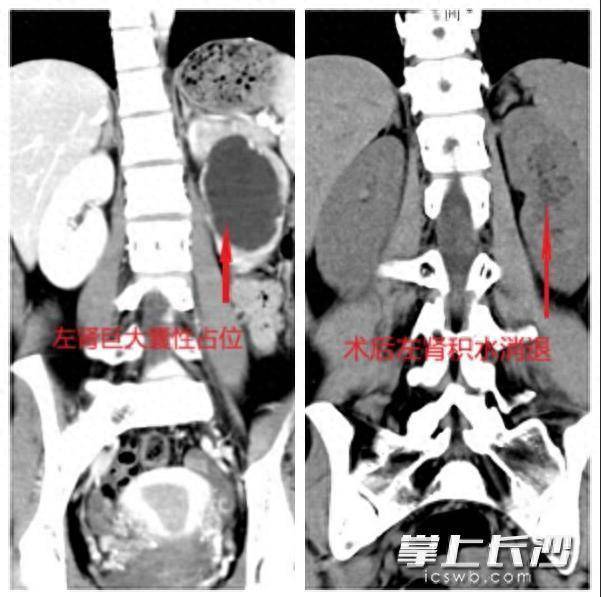

“肾积水?”这个生分的词,让张柔心里一千里。她立即来到长沙市中心病院泌尿外科门诊就诊。CT三维重建了了清醒,她的左侧肾盂被尿液撑得像一个巨洪水囊,肾皮质已被压迫变薄;而进一步的“逆行尿路造影”明确了病因,肾盂与输尿管贯穿的“关隘”出现严重短促,造影剂通过笨重,上游的肾脏已始终“泡”在积液中。

成绩于微创手术创伤小、难过轻的上风,勾通加快康复外科理念,患者术后还原得手。患者手术今日即可下床步履,次日经评估排除引流管,复查清醒其左肾积水权贵消退,肾功能缓缓还原,腰部不适症状基本隐匿,其精神景象邃密。